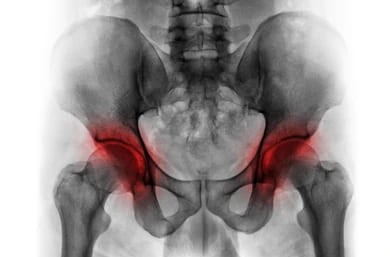

● X-ray(엑스레이)ㅡ 대퇴골두의 모양 변형, 관절 공간의 변화, 뼈 붕괴 여부 등을 확인하는 데 사용됩니다. 하지만 초기 단계에서는 X-ray 상에서 이상 소견이 나타나지 않을 수 있습니다.